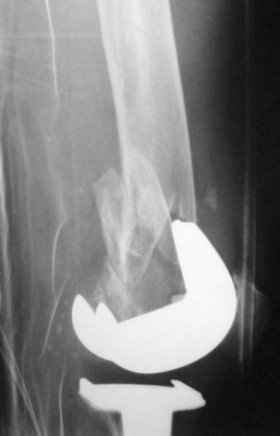

Go antegrade if you have an approriate implant available. Attached is a result of a similar fracture.